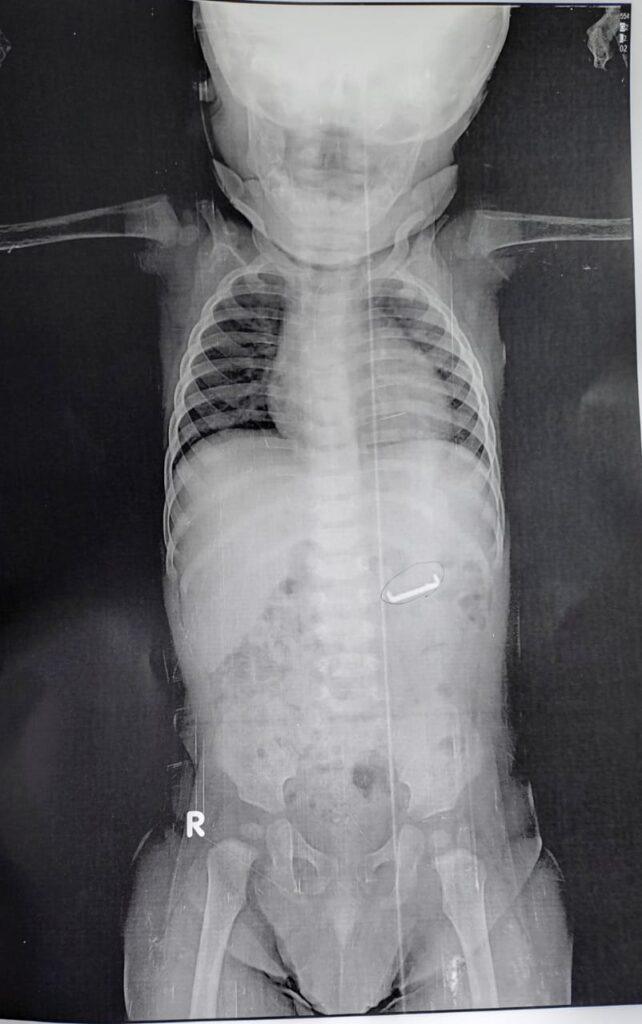

حالة اليوم ، حضر إلى الطوارئ طفل ٨ شهور يعاني من ابتلاع جسم معدني غريب ووجوده بالمعدة ، حيث تم تبليغ فريق الجهاز الهضمي ، وتم الاستجابة السريعة

حيث أن الجسم المعدني حاد ، ويحتاج إلى التدخل السريع ، قبل تحركه من المعدة للامعاء كي لا يزيد من خطورة الحالة واحتمال المضاعفات ، وتم عمل منظار المعدة واستخراج الجسم المعدني بنجاح

وتمت متابعة الطفل بالقسم الداخلي وخروجه بحالة جيدة ، حيث تم عمل المنظار

تحت إشراف أ.د محمد البدري استشاري الجهاز الهضمي، بواسطة ، دكتور إسلام محمد نجيب أخصائي الجهاز الهضمي و بمساعدة ، دكتور محمد طه و د. محمد حسني نواب الجهاز الهضمي ، ومس أميرة زكريا ممرضة المناظير ، مس حنان حمدي مشرفة المناظير .